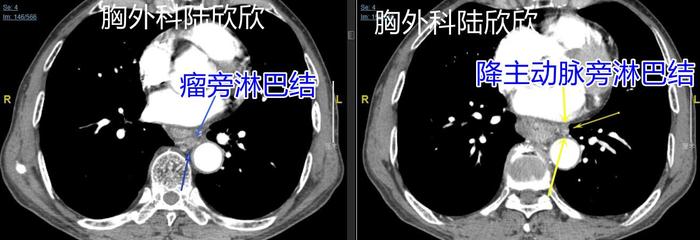

上图为图3。是肿瘤的上极的两个不同平面。上面左边的图,可见一枚瘤旁淋巴结肿大,两个蓝色箭头指示的是一枚瘤旁淋巴结,8毫米,球形,看起来像是转移淋巴结,术后病理证实为转移淋巴结。最右边的黄色箭头指示的是肿瘤周围、降主动脉旁的小淋巴结。这个淋巴结手术是否转移难定,最终术后病理证实为转移淋巴结